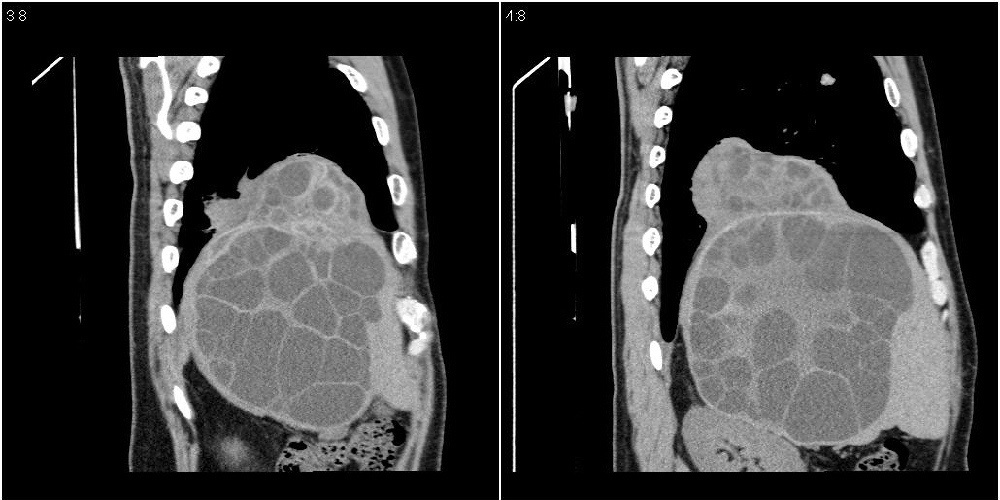

该患者70岁男性,手术后10年,现复查。2008年6月份本人曾经发过一极其类似的病例,只是部位略有差异。

多囊肝

肝脏多房性包虫囊肿

水上浮莲征,肝包虫囊肿。

肝脏及右侧胸腔包虫病。

大囊套小囊!肝脏多房性包虫囊肿